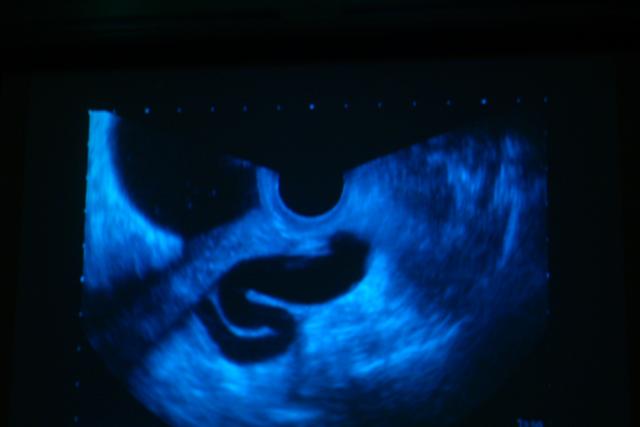

緒音波画像     ltrasonography